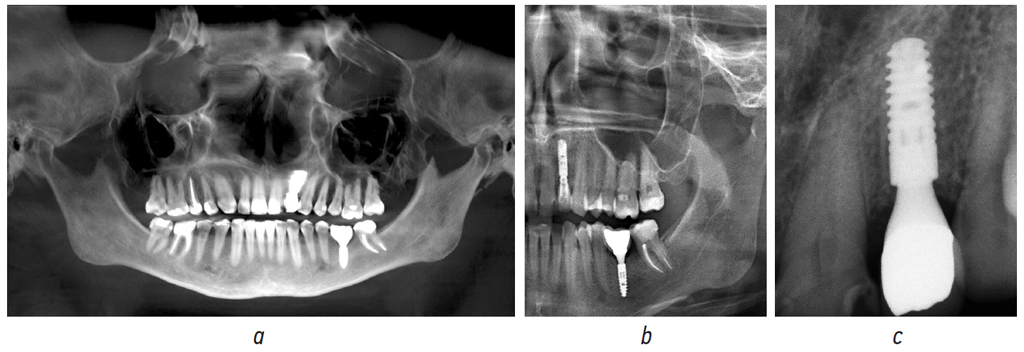

Также выполнено распределение исследований по этапам лечения (рис. 3):

- до начала лечения (диагностика);

- после установки имплантата;

- перед раскрытием имплантата;

- на этапе формирователя десневой манжеты;

- после фиксации постоянной ортопедической конструкции.

Рис. 3. Рентгенологическое обследование одного и того же пациента, выполненное на различных этапах: а — ортопантомограмма на этапе установки имплантата; b — ортопантомограмма с формирователем десневой манжеты на этапе формирования мягких тканей; с — ортопантомограмма после установки окончательной ортопедической конструкции

Fig. 3. X-ray examination of the same patient performed at various stages: a, orthopantomogram at the implant installation stage; b, orthopantomogram with healing abutment at soft tissue formation; c, orthopantomogram after the installation of the final orthopedic structure